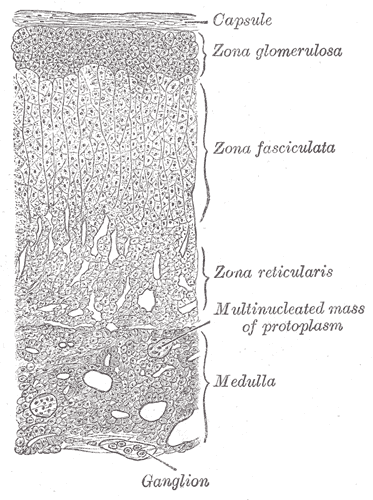

Adrenal Cortex

The largest and outermost portion of an adrenal gland is called the adrenal cortex.

The adrenal gland is composed of three distinct zones which include:

- Zona glomerulosa

- Zona fasciculata

- Zona reticularis

Zona glomerulosa produces mineralocorticoids like aldosterone.

Zona fasciculata creates glucocorticoids like cortisol.

Zona reticularis generates sex hormones like testosterone.

Adrenal Medulla

The adrenal medulla is the innermost part of your adrenal gland.

Adrenal medulla hormones include adrenaline and noradrenaline.

The adrenal medulla is the primary physiological source of catecholamines and are made up of neural crest-derived chromaffin cells.